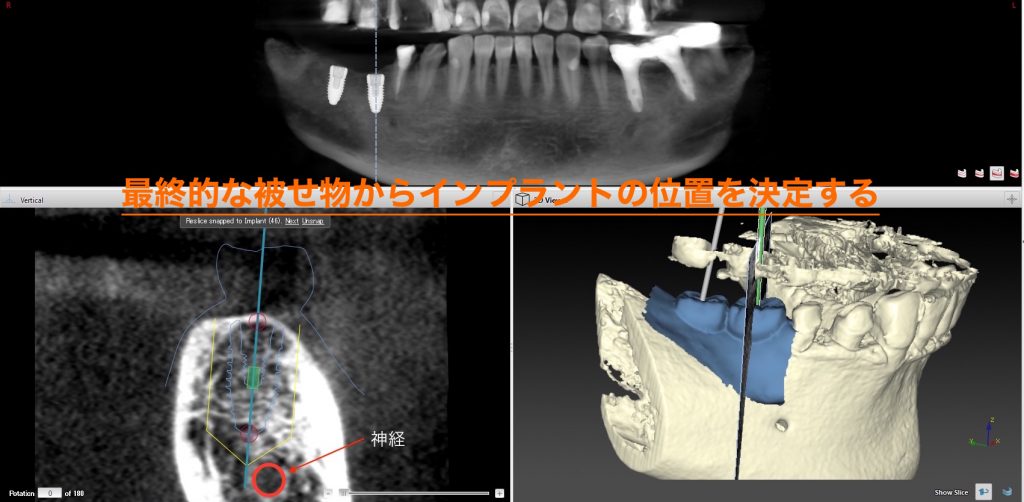

ただ下の奥歯だと、下に神経が走っており、これを傷つけてしまうと下唇に麻痺がでてしまいます。この方の場合は近い距離にある為、CT撮影が必須で2本のインプラントが必要である事からノーベルガイドを使用する事になりました。

②CTデータと重ね合わせて、インプラントの位置を決定し、データを送る

先ほどの最終的な被せ物のイメージとCTを重ね合わせてインプラントの計画をします